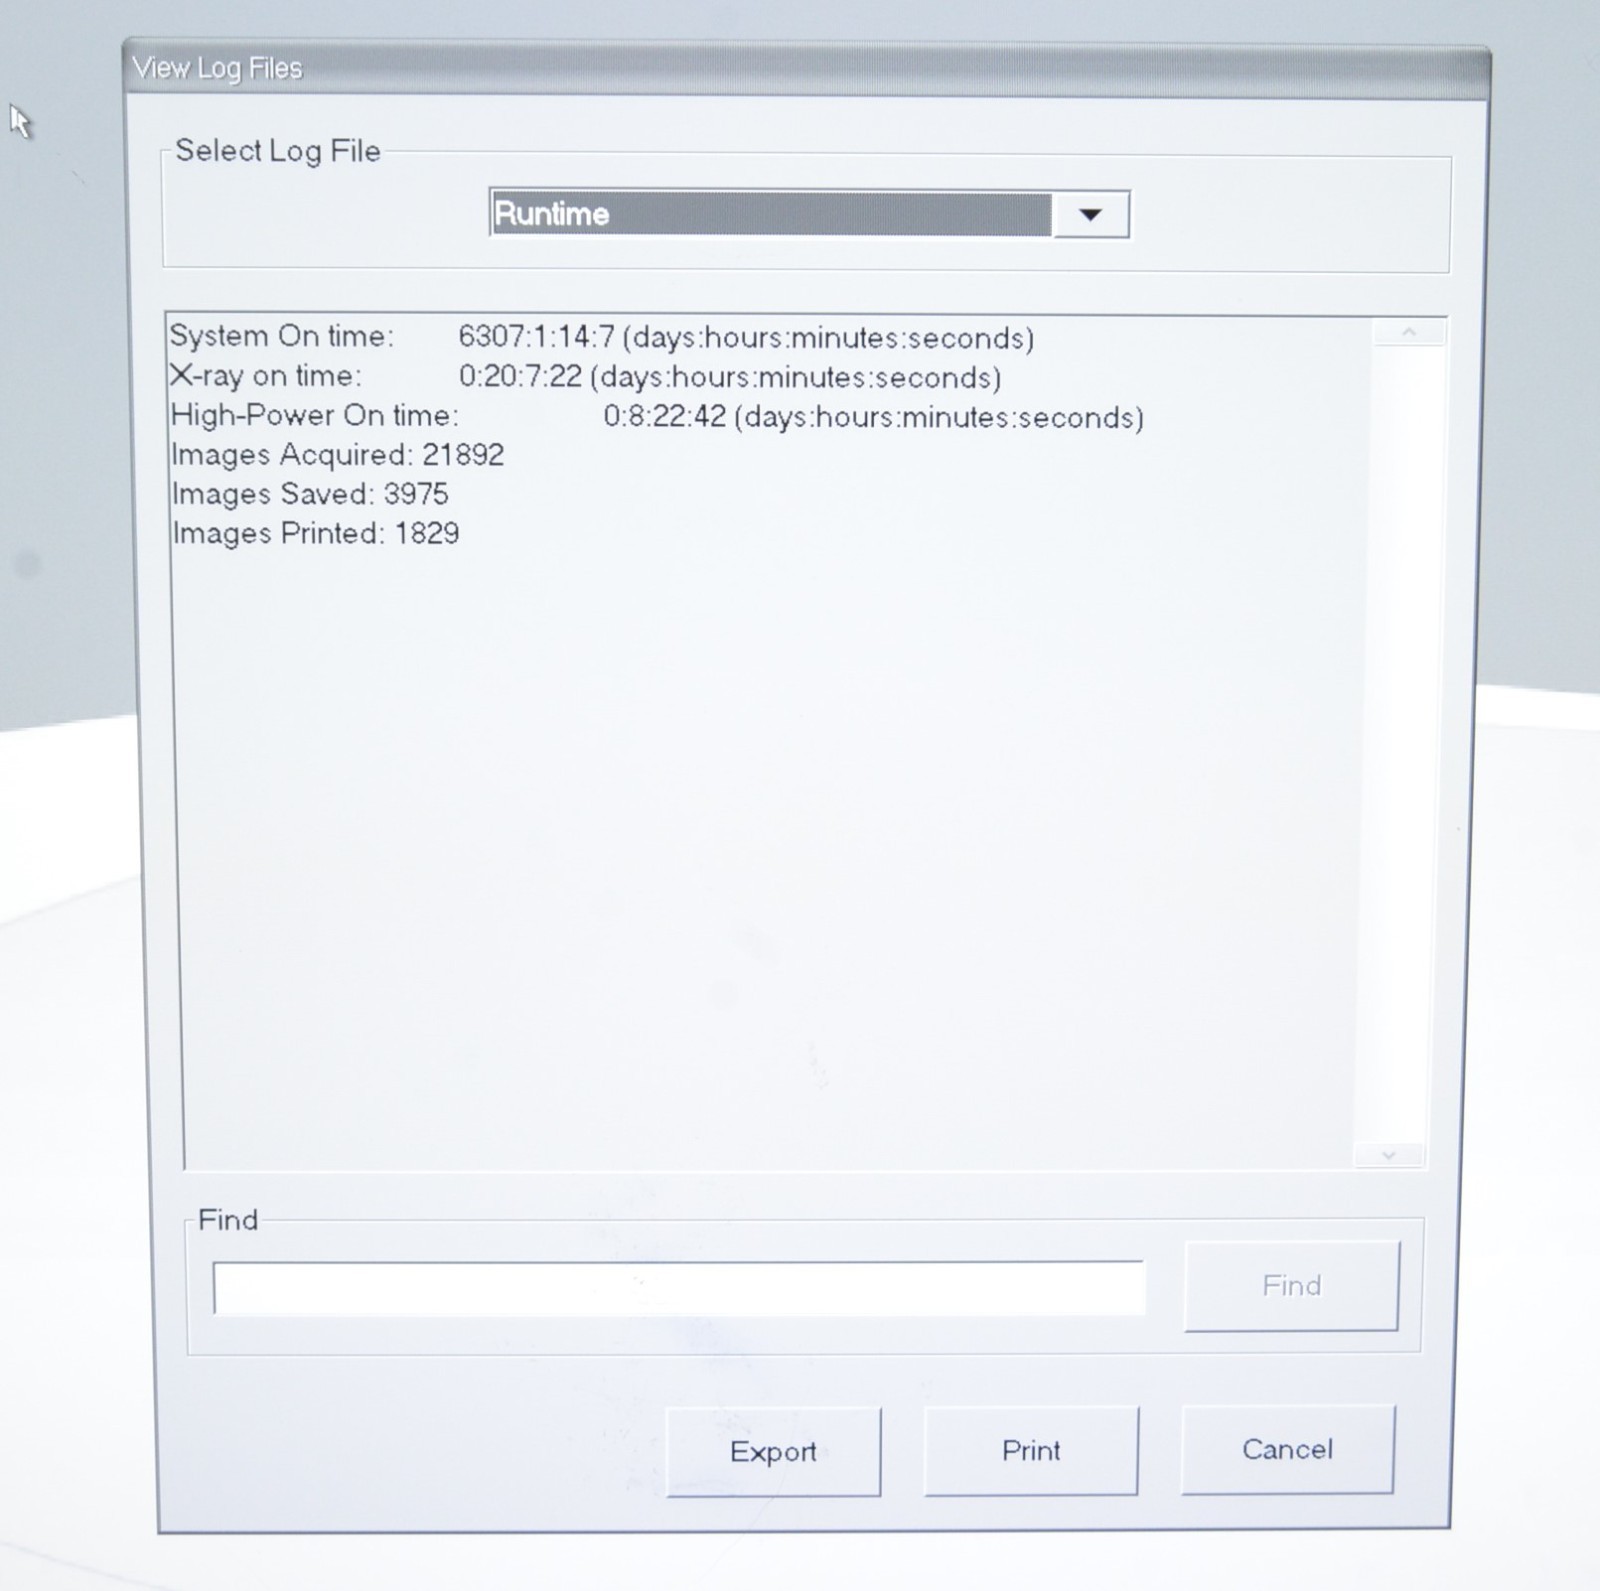

This Hologic Fluoroscan InSight 2 C-Arm X-Ray System 2009 W/ Wireless Footswitch is in good working condition. The system powers on properly. The display screen produces a clear image and all buttons respond properly to selection. All connection points are clean and in good condition. The arm adjusts properly. The images acquired is 21,892. There is a crack in the plastic casing. There are some scuff marks and chips in the paint from previous use (see photos). The screen has some scratches and the image intensifier cover is cracked. The D.O.M is June, 2009 and has Insight software version 3.1.2 installed. This unit comes with a 30 day satisfaction guarantee. Includes everything in the pictures and nothing else.